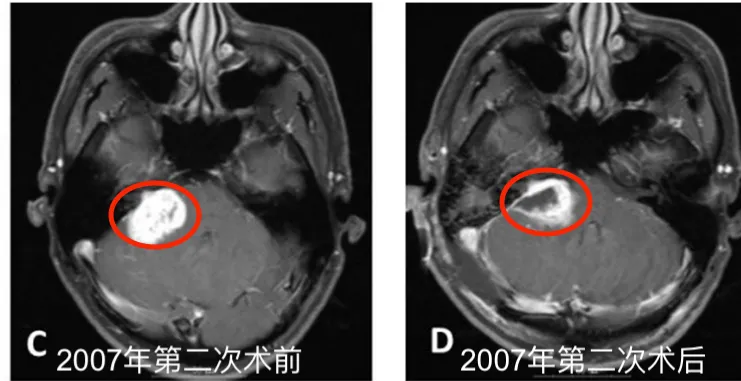

2007年5月:伽玛刀治疗效果未达预期,肿瘤再次生长,他不得已接受了第二次开颅手术。

2007年5月第二次术前MR图像;D.术后1个月图像。